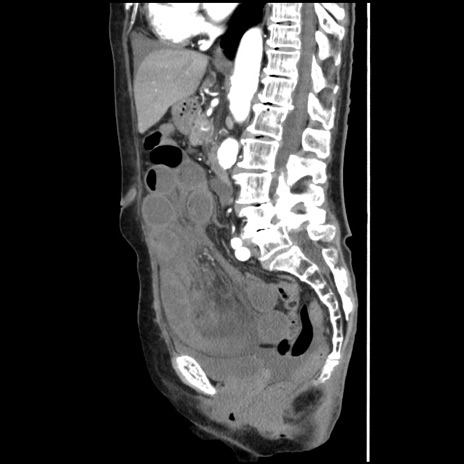

症例1(矢状断像)

【症例】80歳代女性

【主訴】腹痛

【現病歴】8時間前から腹痛あり来院。

【既往歴】糖尿病、脂質異常症、子宮体癌にて子宮全摘術

【身体所見】意識清明・会話良好だが腹痛で苦悶様、全腹部にわたって反跳痛と圧痛あり

【データ】WBC 13600、CRP 0.14、LDH 224、CK 90